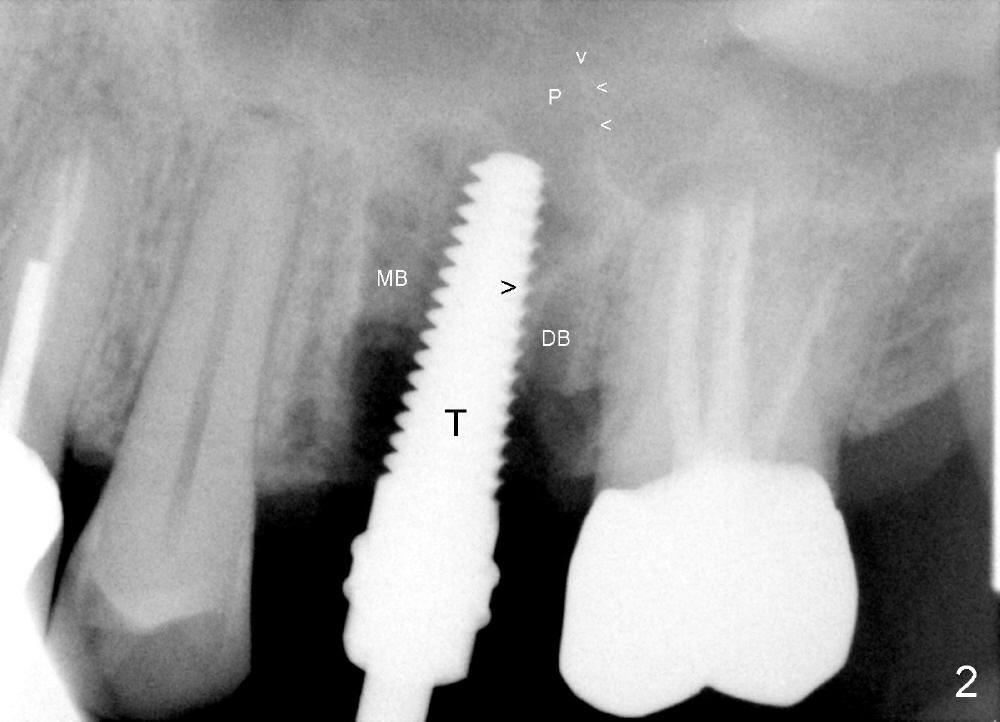

The upper left 1st molar is extracted with sectioning. The septum is large. A surgical fissure bur is used to initiate an osteotomy in the middle of the septum (Fig.1 <; P: palatal socket, MB: mesiobuccal socket), followed by tapping with resistance a 2 mm osteotome ~ 8 mm into the septum. It is tougher to drive 3 mm osteotomy. A 2.5 mm reamer is used to enlarge the osteotomy at 50 RPM at the same depth. Then it is relatively easy to tap 3 and 4 mm osteotomes at ~ 8 mm into the septum. A 4.5x17 mm tap is inserted 8 mm deep with binding to the septum. PA is taken (Fig.2). It appears that the sinus floor (black >) has been penetrated, but the osteotomy has not reached the apex (white >) of the palatal (P) socket. Then the tap is advanced ~ another 3 mm. When the tap is removed, the osteotomy (Fig.3 O) is slightly toward the buccal aspect of the extraction socket, but it has intact wall, including the mesiobuccal (>). The apex of the ostoetomy has no bone, but there is no air leakage. The next tap, 5x17 mm, is inserted shallower (~ 8 mm in the septum; to reduce potential trauma) with stability. However, 6x17 mm tap at the same depth does not obtain stability, since the osteotomy deviates severely mesiobuccally (Fig.4 arrow) with breakdown of the mesiobuccal wall. So the osteotomy has to be deeper in order to achieve stability of 6x17 mm tap (by engaging into more apical bone). A 7x17 mm tap is then intended to be inserted to close the socket as much as possible, but as it is being inserted, the osteotomy is more severely deviated and tilted mesiobuccally with the original mesiobuccal wall further being broken down (not shown). It appears to compromise stability. Mixture of autogenous bone from reamer, allograft and synthetic bone is placed in the mesiobuccal and palatal sockets before placement of the 6x17 mm implant (Fig.5 I). Unfortunately some of graft blocks the apical osteotomy. To clear the blockage, some of previous osteotome and taps are re-inserted. The result is in fact beneficial, as bone graft (G) is pushed upward. Prior to implant placement, nose blowing test does not produce air leakage. More allograft is placed in the coronal portion of the sockets (Fig.6 G); an abutment with precut slots is placed (A) with intention of better holding perio dressing in place after placement of a collagen dressing (Fig.7 M). A temporary crown may be placed when the perio dressing is dislodged. The provisional is to keep the membrane and bone graft in place. The patient returns for follow up 1 week postop. He is symptom free. The abscess appears to be resolving (Fig.8 >); the perio dressing remains in place.